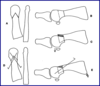

two different types of impants

- Hemi

- Base of proximal phalanx replaced

- Total

- Base of proximal phalanx and 1st met head removed

- One component (one piece spans entire jt)

- Two component (two different pieces)

what implant acts as dynamic spacer?

total flexible hinge implant

- Made of silicone

- Has stems for proximal phalanx and 1st met with central hinge

- Can face hinge dorsally or plantarly

what are grommets?

- Thin titanium shield that fits over stem

- Protects silicone from

- Shearing forces

- Sharp bone edges

which type of implant allows greater postop ROM

two compenent system

(replaces base of proximal phalanx and 1st met head)